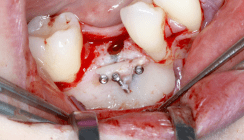

Nach einer Latenzphase von sieben Tagen begann die Distraktion mit 1 mm pro Tag, aufgeteilt in mehrere Einzelaktivierungen unter engmaschiger Kontrolle. Nach Erreichen der vorgesehenen Endposition begann die Konsolidierungsphase (Abb. 4). Der Distraktor wurde nach acht Monaten entfernt und es erfolgte die Implantation in Regio 32 und 42 mit lokaler Augmentation (Abb. 5a+b). Nach einer weiteren Einheilphase von fünf Monaten wurden die Implantate freigelegt und das Weichgewebe mittels eines freien Schleimhauttransplantats vom Gaumen optimiert. Die prothetische Versorgung konnte anschließend festsitzend mit einer implantatgetragenen Brücke von 32-42 realisiert werden (Abb. 6).